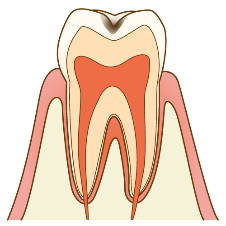

C0

エナメル質にむし歯の穴がなく、白濁、白い模様、着色があるむし歯。

予防・治療:口の中のお掃除や食習慣に関してアドバイスを行うとともに、3~6か月の間隔で定期的に経過観察をしていくことをオススメします!必要に応じてフッ化物塗布などを行います。

C1

歯の表面のエナメル質にだけ小さなむし歯の穴があるむし歯。